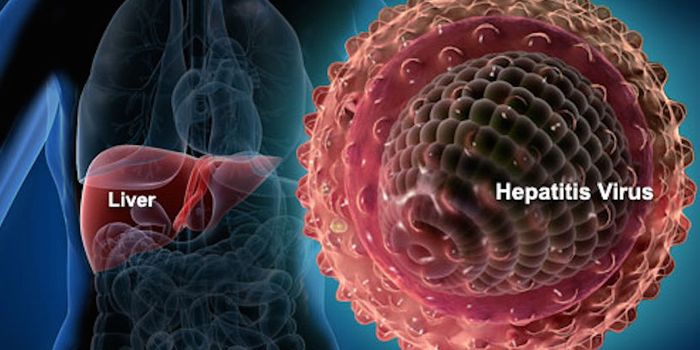

APR 08, 2015ImmunologyAn over-the-counter drug indicated to treat allergy symptoms limited hepatitis C virus activity in infected mice, accord ...

OCT 06, 2015ImmunologyThe Nova Scotia Health Authority in Canada is leading a hepatitis C study at the Prince Edward Island's (PEI) provin ...